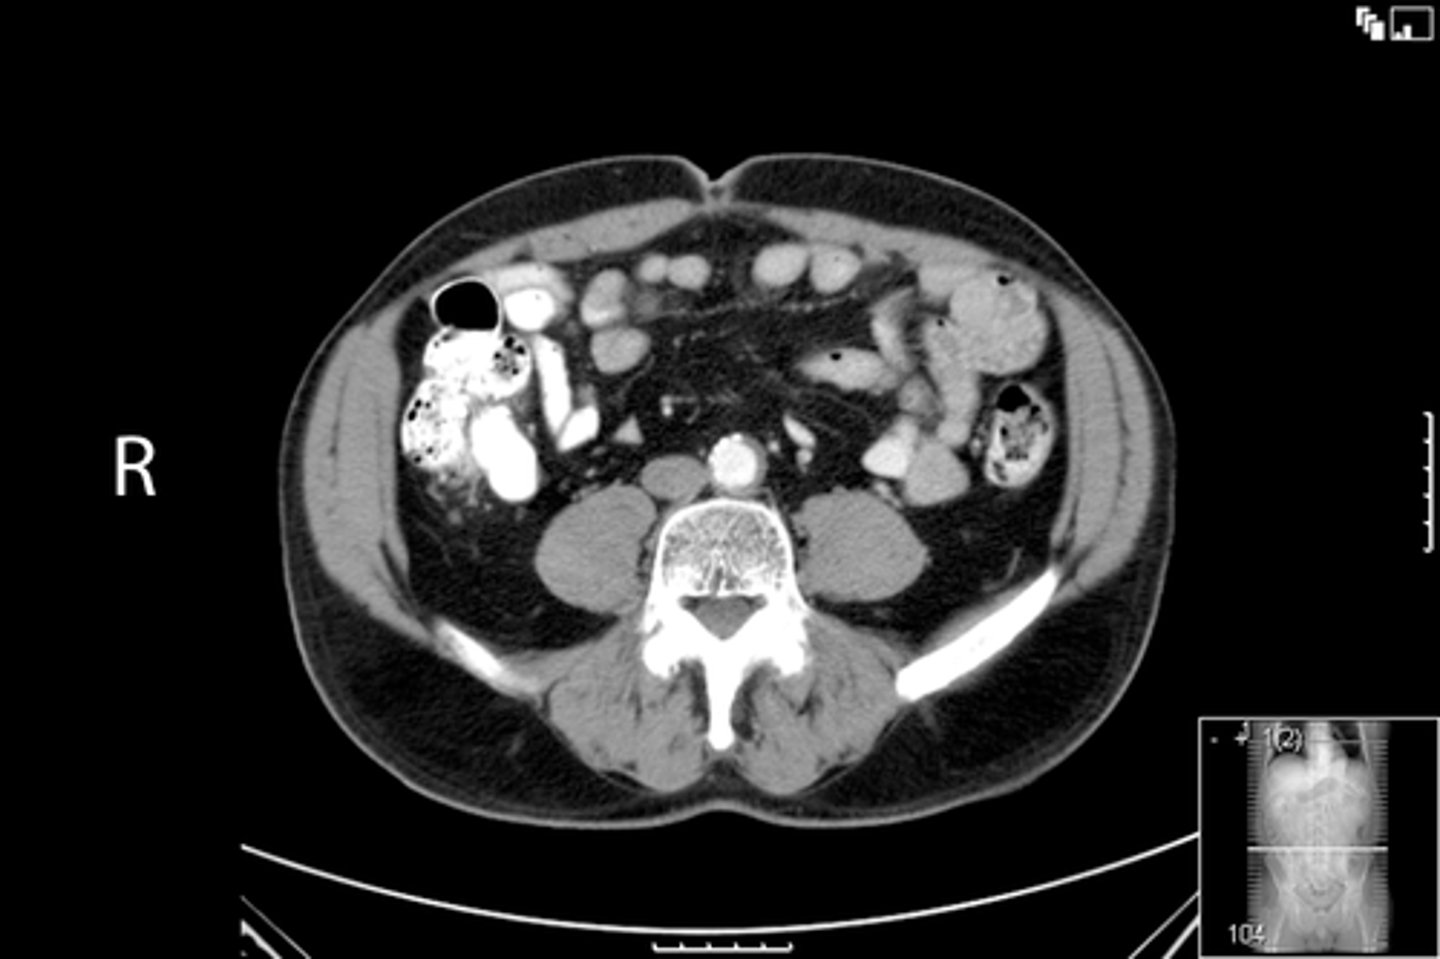

Axial male pelvis CT

What is the image?

Aorta

What is indicated in the image?

Cecum

IVC

L ilium

L psoas muscle

R ilium

R psoas muscle

R rectus abdominis

Terminal ilium